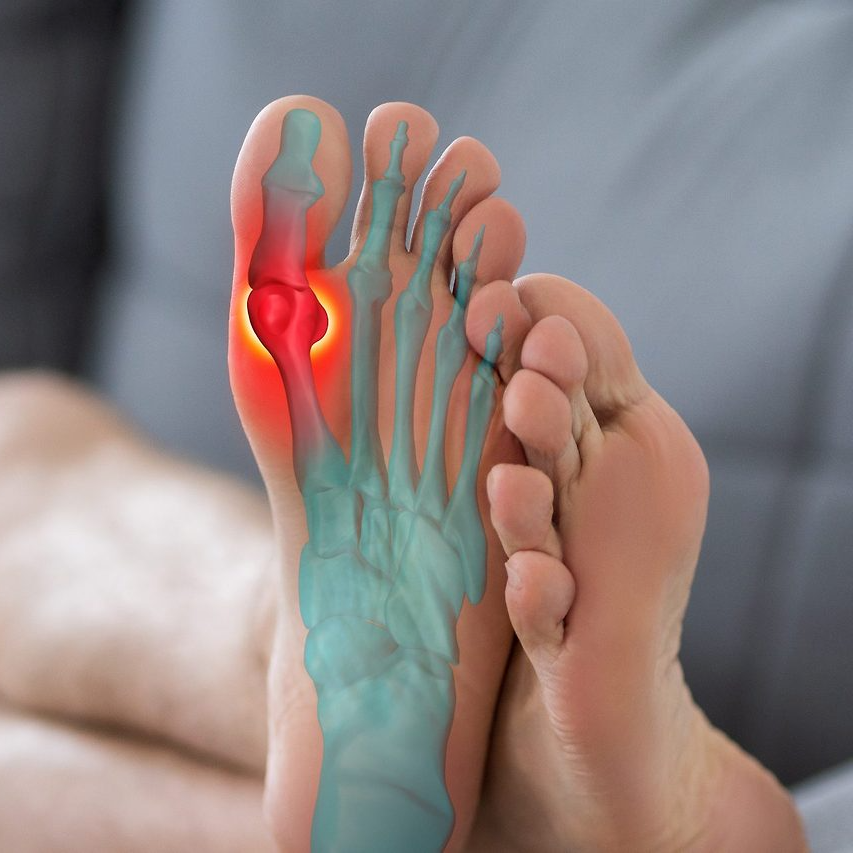

발가락 골절 후 합병증과 후유장해

새끼발가락은 뼈가 작아 회복이 빠르지만, 잘못 붙는 경우 변형이 남거나 걸음걸이에 영향을 줄 수 있다. 간혹 뼈가 굳지 않아 통증이 지속되면 후유장해 진단을 받을 수도 있다. 후유장해가 인정되면 보험금이 추가 지급된다.

- 변형 또는 각변형으로 인한 기능제한 시 3~5% 장해율 인정

- 통증 및 운동제한 시 1~3% 범위 내 인정

- 인공핀 잔존 시 향후 제거 수술 필요 가능성

후유장해 보험금은 약관상 지급률에 따라 수백만 원까지 받을 수 있다. 따라서 치료가 끝난 뒤에도 증상이 남는다면 정형외과 전문의의 진단서를 다시 제출하는 것이 좋다.